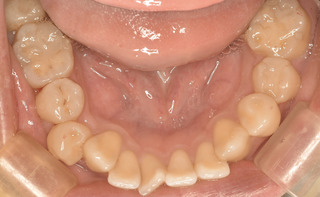

金属から白い詰め物へ

ナチュラルに詰められたかと思います。

自然な感じを再現。溝にステインで周囲の歯と一体感を持たせています。

治療後